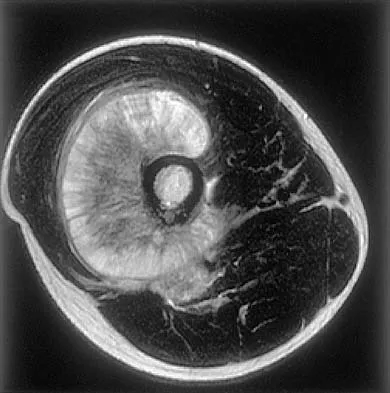

Figures 35a and 35b show the axial T2-weighted and coronal T1-weighted MRI scans of a patient who has enlargement of the right thigh. What is the most likely diagnosis?

The images show a large, almost circumferential, mass surrounding the diaphysis of the femur. The intramedullary signal is normal with minimal cortical destruction, both findings that should be abnormal in conventional osteosarcoma and Ewing's sarcoma. There are very low-signal striations representing osteoid formation that would have a sunburst radiographic pattern. This indicates an osteogenic lesion. Myositis ossificans is not indicated because studies would reveal zonal ossification starting in the periphery rather than the more central pattern seen in this patient. This appearance is typical for periosteal osteosarcoma.